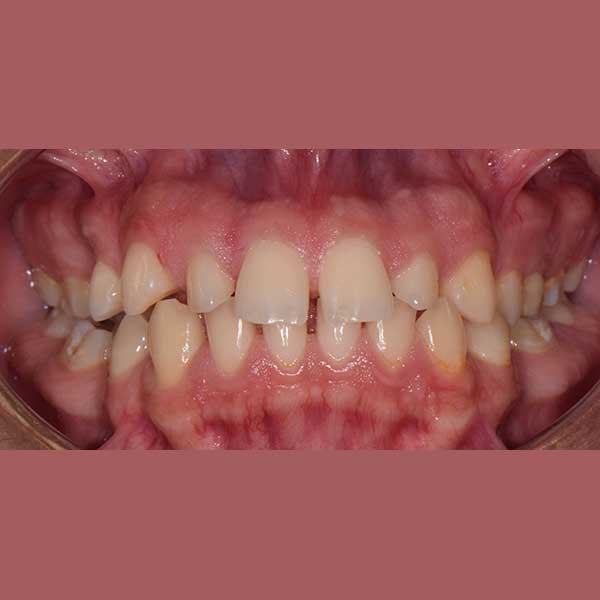

AFTER

Our friend’s case was treated with fixed braces, closing the frontal spaces and returning them to their original position. In the second stage, it was agreed to implant the missing back teeth.